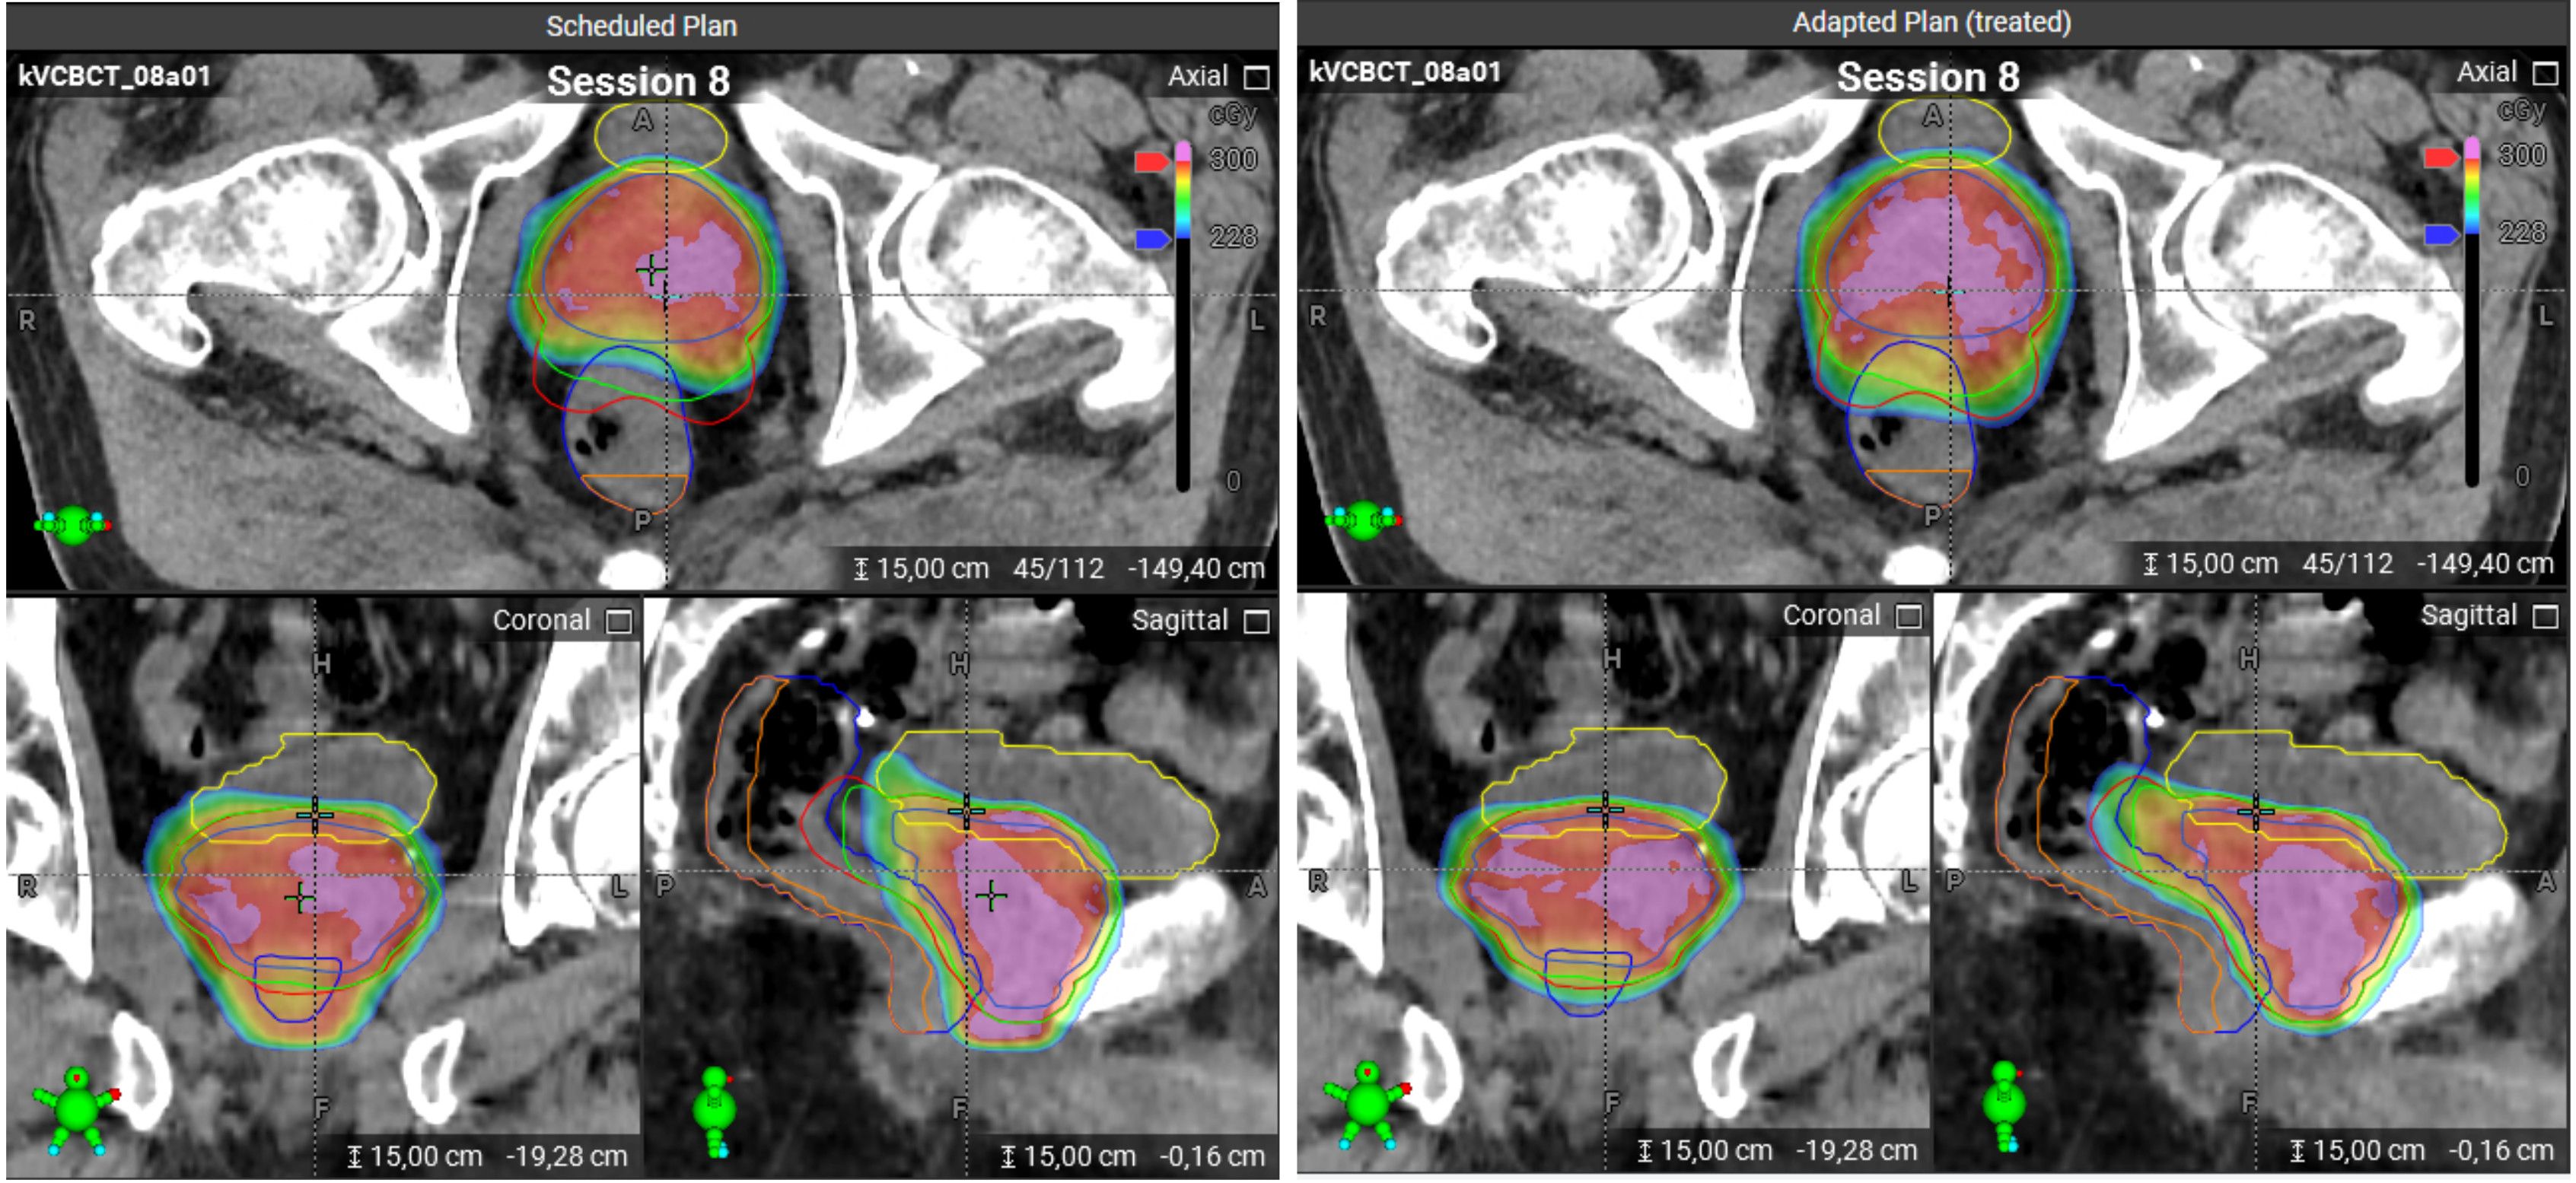

At each treatment session, the patient is positioned and a CBCT scan is acquired. Following a quality check of the image, the system automatically propagates the planning contours to the CBCT of the day. These propagated contours must then be reviewed and, if necessary, edited by the user. Using deformable image registration, the CBCT anatomy is mapped back to the planning CT to preserve Hounsfield unit accuracy (synthetic CT). On this basis, two dose distributions are calculated: (1) the dose from the scheduled (non-adapted) plan applied to the current anatomy, and (2) a newly re-optimized adapted plan, generated using the original treatment intent and constraints, tailored to the anatomy of the day (Figure 1).

Figure 1. Scheduled and adapted plans on a CBCT image for the same treatment session. Left panel: The scheduled plan. Right panel: The adapted plan. The color scheme for the contours: bladder – yellow, rectum – dark blue, PRW – orange, PTV/SIB1/SIB2 – red/green/blue. The dose distributions are visualized using a color wash, where blue corresponds to 2.28 Gy and red to 3 Gy. Doses above 3 Gy are indicated in pink. The scheduled plan shows strong underdosage for PTV and SIB1 which could be compensated with the adapted plan, as can be seen in sagittal and axial views.